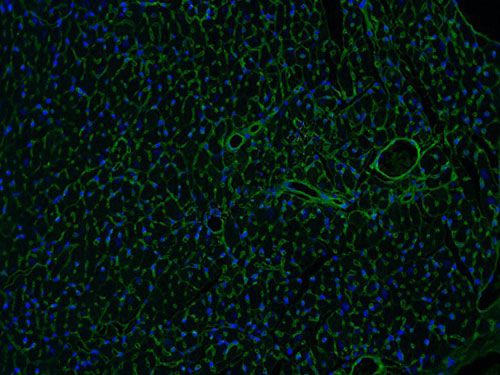

麥胚凝集素(WGA)是從谷物中提取出來,可以特異性的結(jié)合心肌細(xì)胞膜上的一種糖蛋白,二者結(jié)合起來可以將心肌細(xì)胞膜染出來。WGA可以把心肌細(xì)胞膜染出來,這樣是否肥大的細(xì)胞從圖像與正常組的對(duì)比就可以看出,也可以用專門的軟件對(duì)染出的細(xì)胞進(jìn)行直徑、面積等的測(cè)量,能夠分析心肌細(xì)胞是否肥大。

實(shí)驗(yàn)結(jié)果展示:

WGA染色-小鼠心臟

脫蠟至水-抗原修復(fù)-滴加WGA工作液,溫箱孵育30分鐘-染核封片-顯微鏡鏡檢